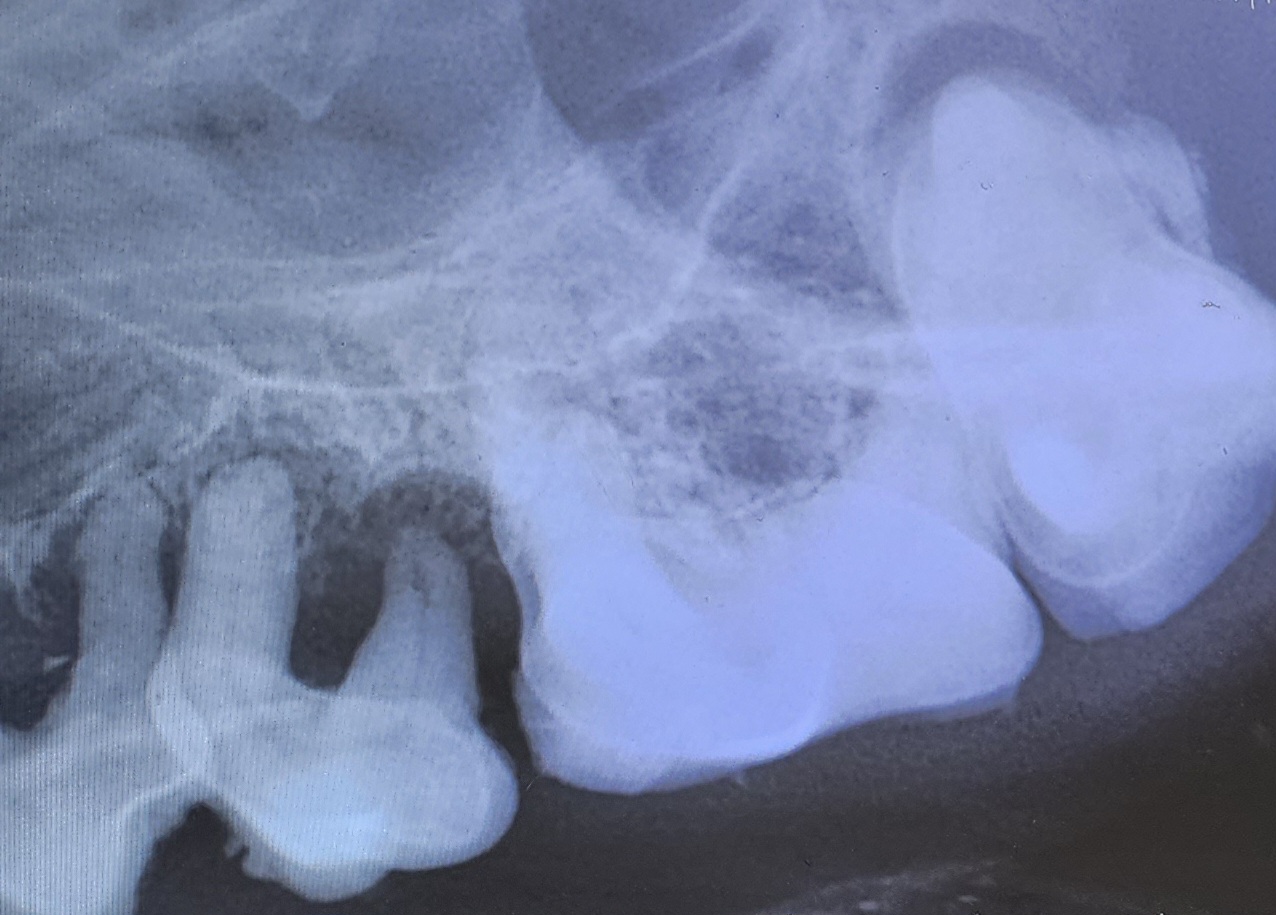

Dental Radiographs

We utilize dental radiographs for all patients. We take radiographs of your pet’s entire mouth and also take post-extraction radiographs to ensure all parts of the diseased teeth are removed.